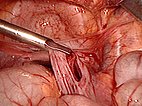

View to the right lower abdomen. Grasping forceps pointing to a cyst in front of the cecum and appendix.

The peritoneum to the posterior abdominal wall is opened and all the cysts are gradually dislodged and removed.